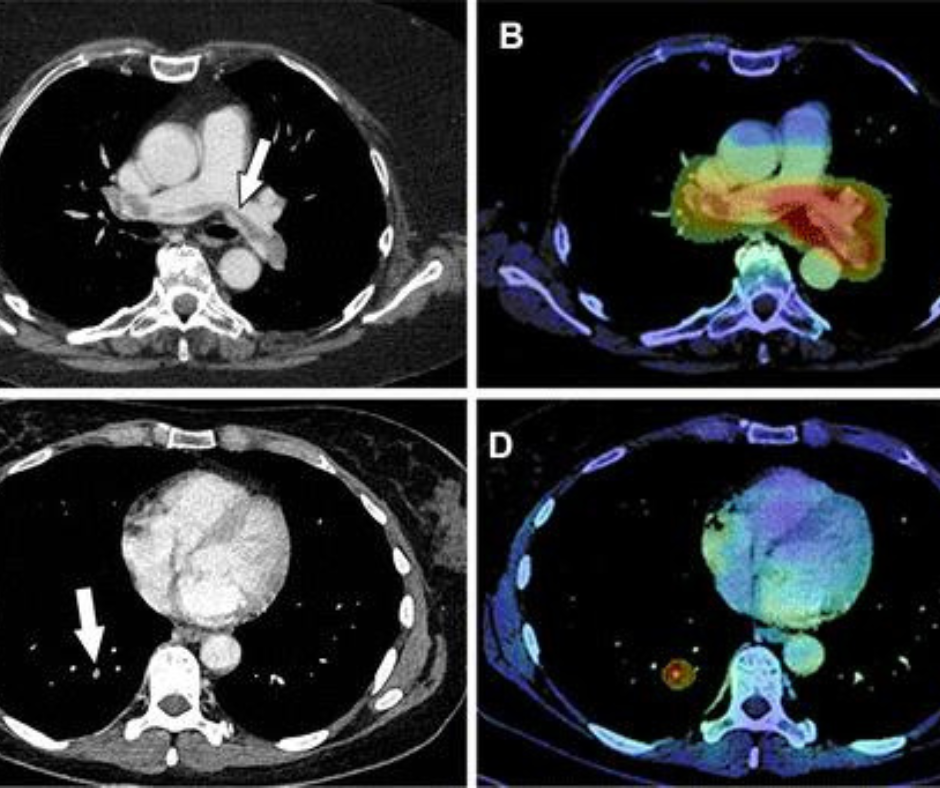

Изображения предоставлены Radiology: Cardiothoracic Imaging .